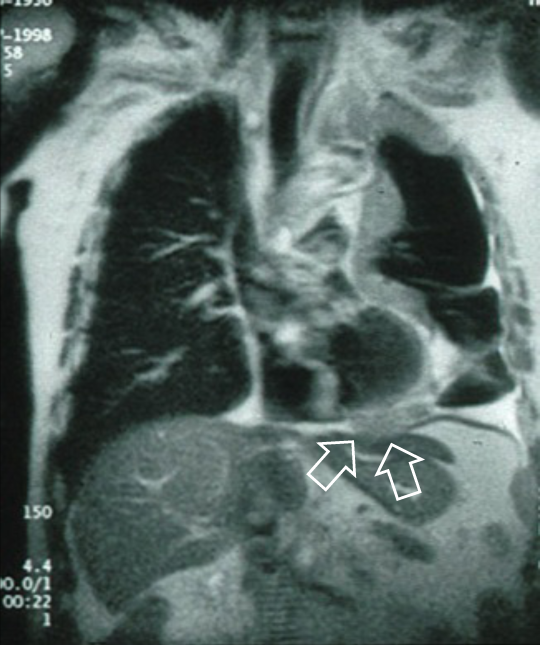

胸膜中皮腫(T4):横隔膜下浸潤

MRI像では腫瘍が横隔膜下に達していることが確認できる(T4)。